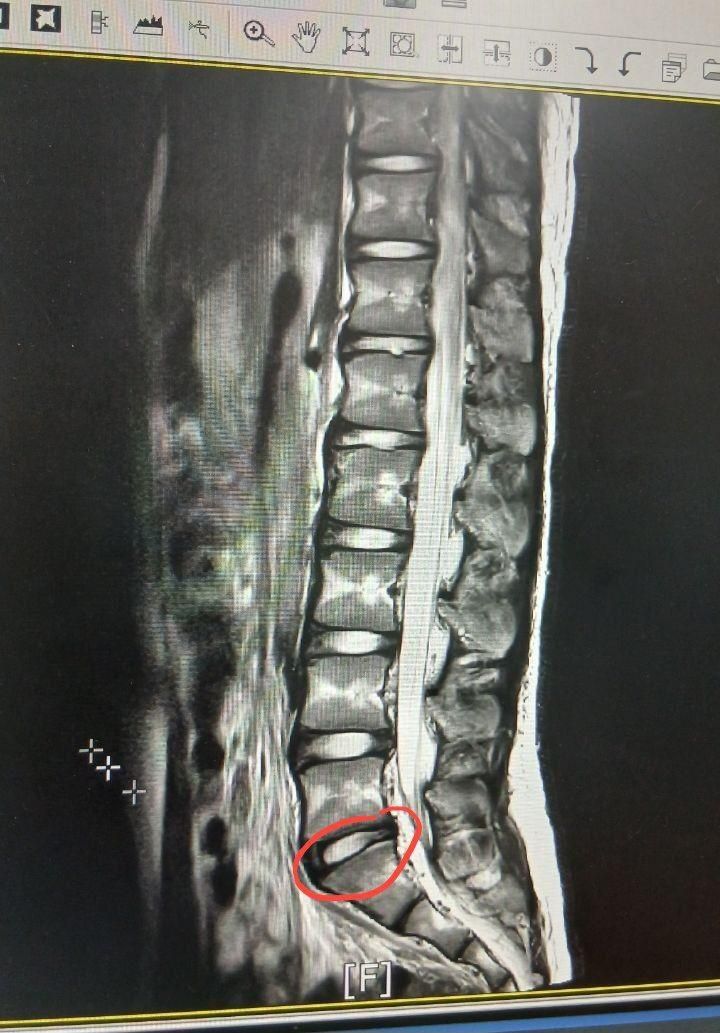

디스크 팽윤인가요? 어떤 디스크 문제일까요?

15살 남자인데요 제가 요추쪽 허리가 아픈지 5개월쯤 되었는데요. 그래서 병원에 MRI 찍어보니 병원에서 디스크 문제가 아니고 근육이나 인대 그런게 문제라고 하네요.

하지만 의사 선생님 의견도 알겠지만 저는 5개월이나 아팠고 아무리 근육통이라고 하더라도 통증이 10점 중 4점인 상태가 5개월동안 지속 되었고 MRI에 보면 디스크가 살짝 나와 있어서 여기 의사 선생님에게도 자문을 구합니다.

L5와 S1사이 쪽 디스크가 살짝 튀어나와보여요

L4쪽와 L5사이도 살짝 튀어나와 보이긴 하네요

사진상으로 많은걸확인할수는없지만 디스크의정도가 심하지는 않아보이는데요 따라서 통증과불편감이있다면 평소 운동과 스트레칭을 통해서 관리하는 것이 중요합니다

현재 mri상 디스크 팽윤과 돌출 사이로 의심이 가지만 좀 더 확실한건 전문의에 소견을 들어보시길 바랍니다.